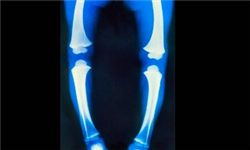

عوامل مهم در مدت زمان درمان زانو پرانتری

مدت زمان درمان زانو پرانتزی (گنو والژوم) به چند عاملی بستگی دارد که در ادامه توانبخشی ایرانیان برای شما شرح میدهد: